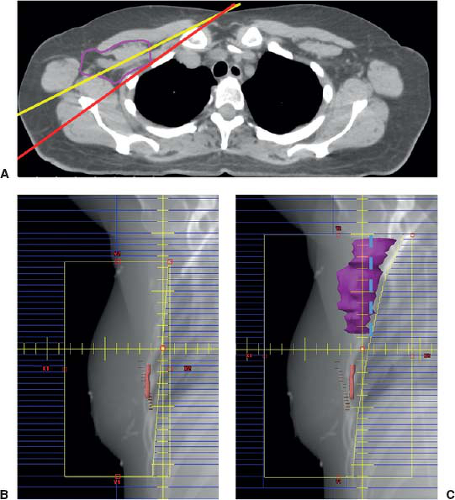

Lumpectomy patients, cT1-2N0, ≤2 nodes found on SLNB, no gross ECE: In clinically node-negative patients with T1–2 tumors undergoing upfront surgery with lumpectomy and planned for whole breast radiation, sentinel node biopsy is sufficient, as described in the previous section. The radiation oncologist should ensure that the entire level I and II axilla is encompassed in the radiation tangent portal, as shown in Figure 29-1. The decision for extended radiation to include the supraclavicular and internal mammary nodes, RNI, should be made based on careful review of patient and tumor characteristics, such as patient age, tumor size, and tumor biology, as described in the cases below.